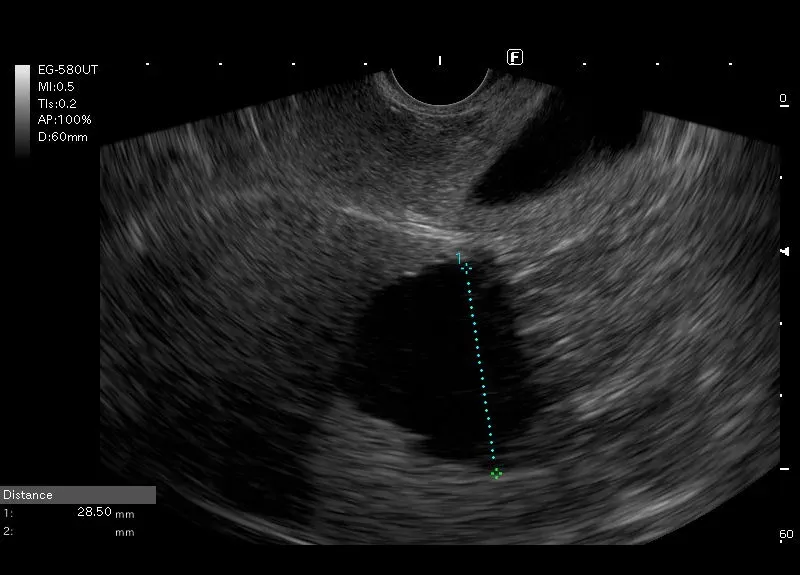

Widoczna w wątrobie

bezechowa, owalna przestrzeń, bez widocznego przepływu w opcji PD - torbiel

wątroby.